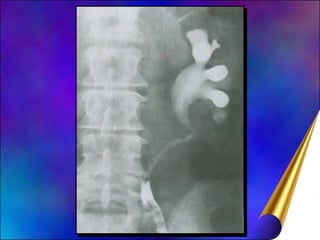

Diagnóstico Hematúria Indolor, cólica renal (coágulos) Obstrução: dor surda e contínua Tu assintomático (descobertos acidentalmente) U.Excretora: defeito de enchimento bacinete, cálices

Diagnóstico Diferencial Coágulo, cálculo radiotransparente, bola de fungo, papila necrótica Cistoscopia Possibilidade Tu vesical concomitante Citologia urinária ajuda se positiva (muitos falso-negativo) Estadiamento: CT tórax, abdômen

Diagnóstico Hematúria Indolor,cólica renal (coágulos) Obstrução: dor surda e contínua Tu assintomático (descobertos acidentalmente) U.Excretora: defeito de enchimento bacinete, cálices

Diagnóstico Diferencial Coágulo,cálculo radiotransparente, bola de fungo, papila necrótica Cistoscopia Possibilidade Tu vesical concomitante Citologia urinária ajuda se positiva (muitos falso-negativo) Estadiamento: CT tórax, abdômen